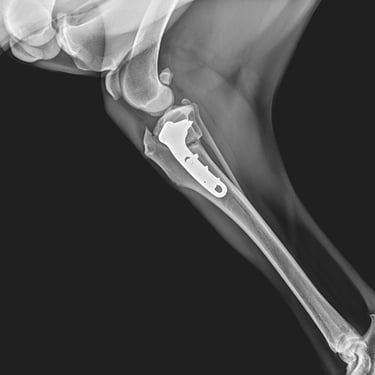

Placas y tornillos: permiten la fijación rígida del foco de fractura, logrando compresión interfragmentaria o neutralización de fuerzas. Son ideales para fracturas diafisarias y metafisarias, ya que brindan excelente estabilidad y control de la alineación ósea.

Placas bloqueadas (LCP): sistema de estabilidad angular donde los tornillos se fijan a la placa, formando un constructo rígido que no depende del contacto íntimo con el hueso. Son especialmente útiles en fracturas conminutas o en pacientes con hueso osteopénico.